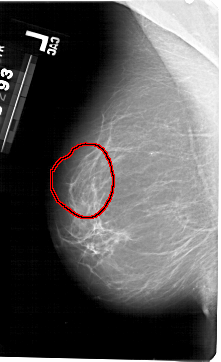

A_1493_1.LEFT_MLO

LEFT_MLO LINES 5416 PIXELS_PER_LINE 3301 BITS_PER_PIXEL 12 RESOLUTION 43.5 OVERLAY

FILE: A_1493_1.LEFT_MLO.OVERLAY

TOTAL_ABNORMALITIES 1

ABNORMALITY 1

LESION_TYPE CALCIFICATION TYPE PLEOMORPHIC DISTRIBUTION SEGMENTAL

ASSESSMENT 4

SUBTLETY 4

PATHOLOGY BENIGN

TOTAL_OUTLINES 1

BOUNDARY